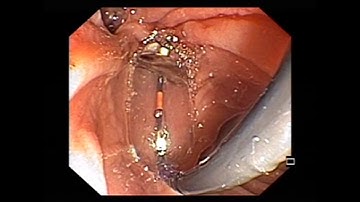

Set-up and Use of the SpyGlass™ DS System’s Digital Controller